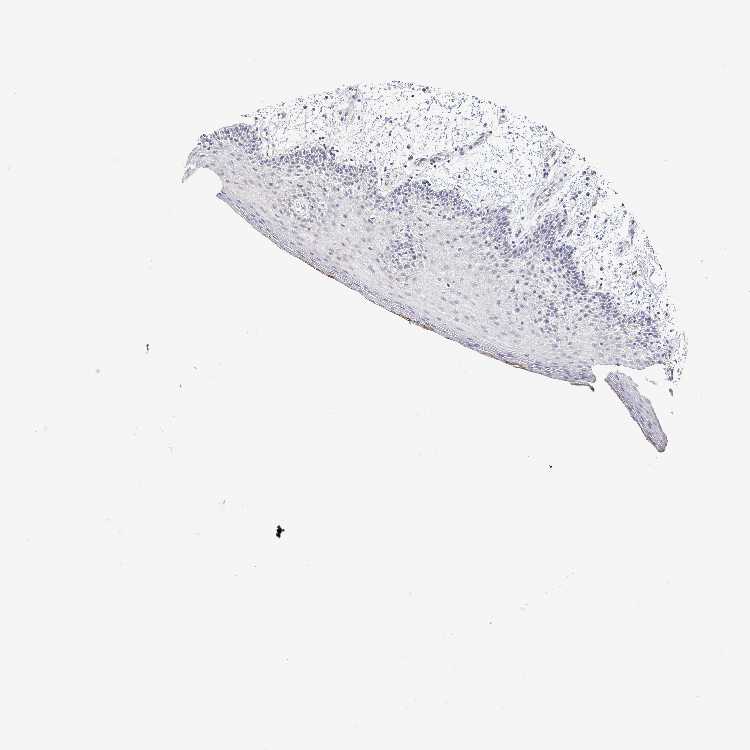

PLCB1